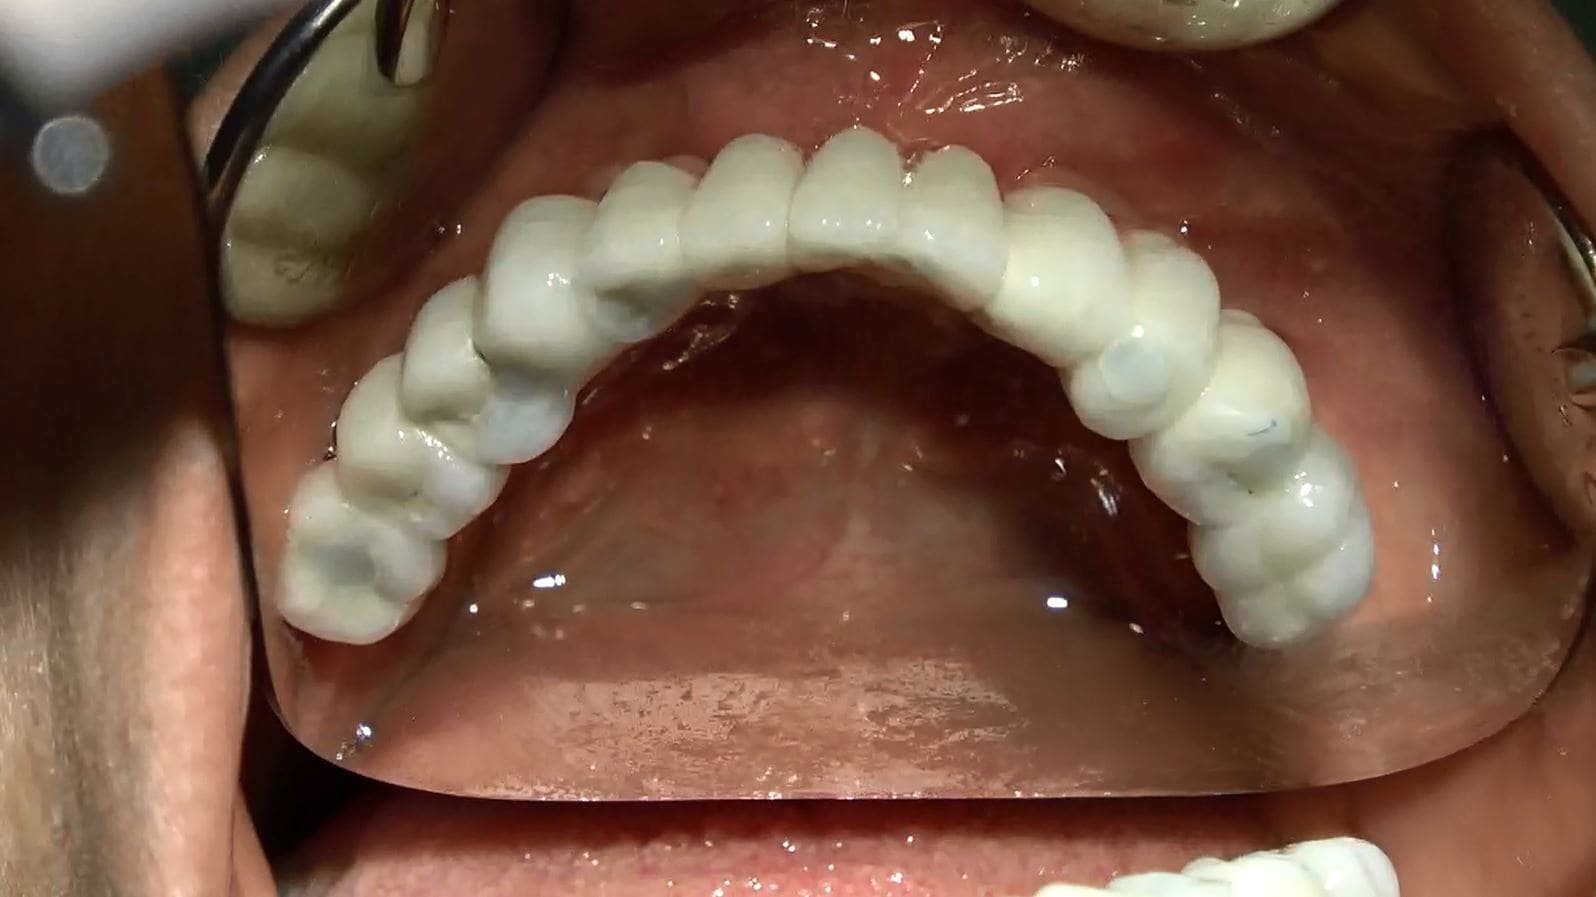

• Il video documenta ogni fase dell’intervento, dalla progettazione personalizzata della griglia sottoperiostea all’applicazione dei singoli impianti e, infine, alla realizzazione di una protesi dentale a carico immediato.

• Accompagniamo il video con una galleria fotografica dettagliata che cattura ogni fase del processo e i risultati finali sorprendenti.

• Dopo un periodo di circa 6 mesi, quando l’integrazione degli impianti è completa, la protesi provvisoria può essere sostituita con una protesi dentale fissa definitiva in ceramica, composta da 14 denti.

Passati 6 mesi di osteointegrazione si sostituisce protesi fisse provvisorie con protesi fisse in ceramica definitiva 14 denti